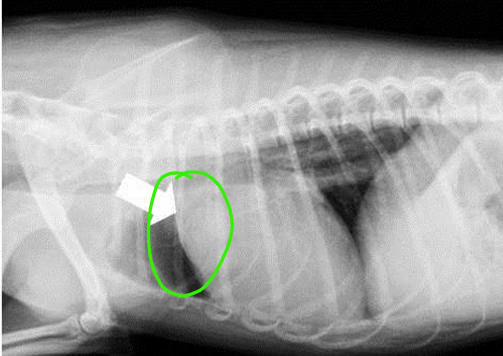

Total situs inversus

Heart is located towards the right side of thorax

Dextrocardia

Mirror image of the thoracic and abdominal organs

Situs inversus